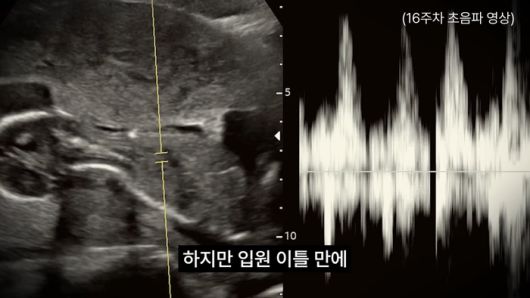

영상에 따르면 비극은 지난 12월 29일 정밀 초음파 검사 중 시작되었다. 모든 것이 정상이라는 말을 듣던 중 갑작스럽게 양수가 줄어들었다는 소견과 함께 응급 이송되었으나, 이틀 만에 양수 수치가 ‘0’이라는 절망적인 통보를 받았다. 강은비는 당시 상황에 대해 “제가 너무 무지해서 제 잘못으로 아기가 고통 속에서 버티고 있다는 말 앞에서 저는 결정을 해야 했습니다”라며 “아기는 태반에 바짝 말라붙어 있었고 더 이상 폐가 발달할 수 없다는 말을 들었을 때 모든 것이 무너졌습니다”라고 회상했다.